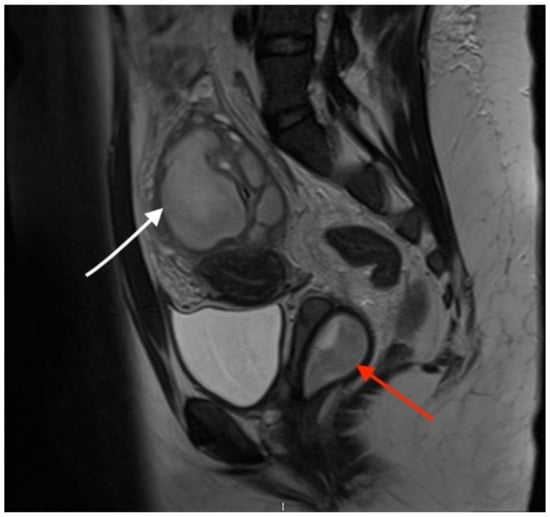

Sagittal T2-weighted MR image showing a vaginal septum with a haematopyocolpos of the obstructed hemivagina and a tubo-ovarian abscess (red arrow indicates the obstructed haematopyocolpos, and white arrow shows the tubo-ovarian abscess). The presence of gas and fluid within the lumen was indicative of a concurrent infection. The patient was initially treated with intravenous antibiotics after the provisional diagnosis of PID. After three days of treatment, she continued to have episodes of pyrexia, the CRP level remained high (242 mg/L) and there were persistently high WCC (16.5 × 109/L) and platelet quantities (500 × 109/L). On the third day after admission, the diagnosis of OHVIRA syndrome was finalised, and the decision was taken to take the patient for surgical intervention to drain the haematocolpos and perform a laparoscopic exploration, to which the patient consented. The next day, the patient underwent an examination under anaesthesia, vaginal septectomy and drainage of the haematopyocolpos. Intraoperative hysteroscopy confirmed the presence of a uterus didelphys bicollis. The cervix of the affected cavity was dilated to encourage continuous drainage. Subsequently, during the laparoscopy, significant pelvic adhesions were noted, involving the bowel being adherent to the uterus, and a large right-sided tubo-ovarian abscess. Laparoscopic adhesiolysis was performed, as well as the drainage of the abscess. The pelvic drain was left in situ at the end of the procedure. She remained an inpatient for four days after surgery. The drain was removed three days after the operation. She was continued on intravenous antibiotics for a further three days before they were converted to oral medication. She no longer had a post-operative spiking temperature, and her pulse normalised two days after the operation. Her CRP dropped to 51 mg/L and WCC to 9.5 × 109/L on the day of discharge. She was followed up in the Gynaecology Clinic with repeat imaging that confirmed the resolution of the tubo-ovarian abscess. She was carefully debriefed about the implications of having uterus didelphys and a single kidney in pregnancy and was further signposted to written information provided by the British Society of Paediatric and Adolescent Gynaecology.